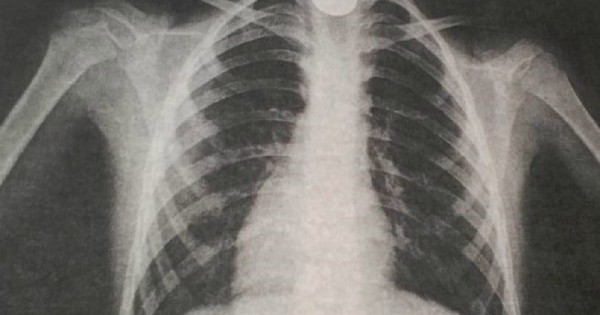

Белгілі болғандай, ойнап отырған 9 жастағы бала байқамай тиынды жұтып қойған. Бір сағаттан соң оның тыныс алуы қиындап, жағдайы нашарлаған. Бұдан соң, ол облыстық көпбейінді балалар ауруханасына жеткізілген. Өкпе жасушаларын түсірген рентгенография қорытындысы өңештің жоғарғы жағында бөгде заттың тұрғандығын анықтаған.